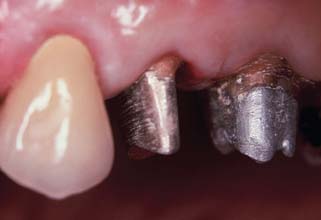

Fig. 12-4 The second premolar has been restored with a cast post and core, before a metal-ceramic crown.

(Courtesy of Dr. R. Webber.)